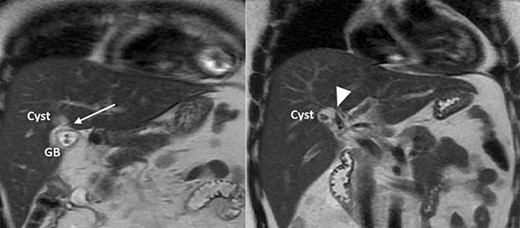

A 35-year-old man presented with a history of recurrent episodes of epigastric pain. Ultrasonography revealed an intrahepatic cyst (Fig. 1), and magnetic resonance cholangiography revealed that the cyst was connected to the cystic duct and right anterior sectoral bile duct (Fig. 2). The patient underwent an endoscopic retrograde cholangiography, which showed that the contrast could fill the cyst (Fig. 3). The laboratory findings, including a complete blood count, showed a white blood cell count of 4200/mm3 (lymphocyte 23%, neutrophil 62%); haemoglobin level of 16 g/dL; platelet count of 215 × 103/ mm3; total protein of 7.8 g/dL; albumin of 4.3 g/dL; total bilirubin level of 0.68 mg/dL; serum aspartate aminotransferase level of 26 IU/L; serum alanine aminotransferase level of 29 IU/L and alkaline phosphatase level of 105 IU/L. Tumour markers, including alpha-fetoprotein, carcinoembryonic antigen and carbohydrate antigen 19–9 were within normal limits. Viral markers for hepatitis B and C were negative. Due to the preoperative diagnosis of a type VI choledochal cyst, with a differential diagnosis of cystic intraductal papillary neoplasm of the bile duct, the patient underwent laparoscopic right anterior sectorectomy to excise the cyst completely. During the operation, after identifying the cystic duct and taking down the fundus and body of the gallbladder from the liver bed, an intraoperative cholangiogram was performed via the cystic duct connected to the cyst. Right anterior sectorectomy was then performed (Fig. 4). The postoperative period was unremarkable, and the patient was discharged on the sixth postoperative day. Pathological examination revealed a cyst with a fibrous wall, dense chronic inflammatory infiltration, lined by columnar epithelium. Mild reactive atypia, associated with marked chronic inflammatory cell infiltration, was noted. No signs of epithelial dysplasia were observed (Fig. 5).

MRCP showing a cyst connected to the cystic duct (arrow) and the right anterior sectoral bile duct (arrowhead).